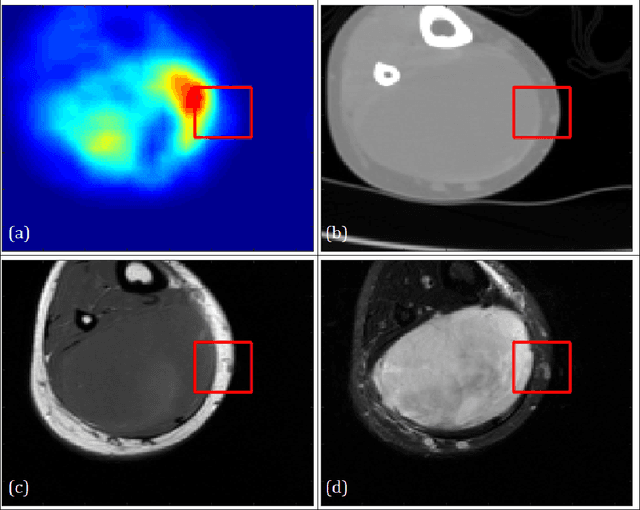

Image analysis using more than one modality (i.e. multi-modal) has been increasingly applied in the field of biomedical imaging. One of the challenges in performing the multimodal analysis is that there exist multiple schemes for fusing the information from different modalities, where such schemes are application-dependent and lack a unified framework to guide their designs. In this work we firstly propose a conceptual architecture for the image fusion schemes in supervised biomedical image analysis: fusing at the feature level, fusing at the classifier level, and fusing at the decision-making level. Further, motivated by the recent success in applying deep learning for natural image analysis, we implement the three image fusion schemes above based on the Convolutional Neural Network (CNN) with varied structures, and combined into a single framework. The proposed image segmentation framework is capable of analyzing the multi-modality images using different fusing schemes simultaneously. The framework is applied to detect the presence of soft tissue sarcoma from the combination of Magnetic Resonance Imaging (MRI), Computed Tomography (CT) and Positron Emission Tomography (PET) images. It is found from the results that while all the fusion schemes outperform the single-modality schemes, fusing at the feature level can generally achieve the best performance in terms of both accuracy and computational cost, but also suffers from the decreased robustness in the presence of large errors in any image modalities.